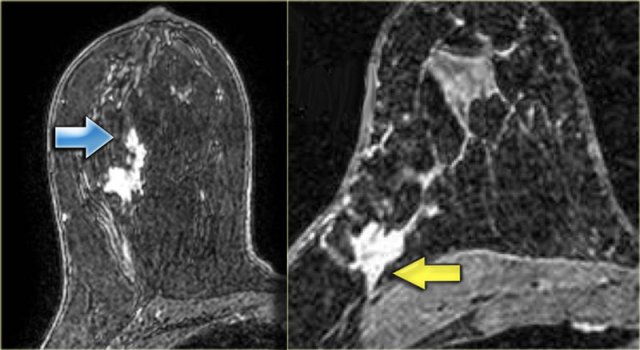

The image on the far left shows an irregular mass with some ductal extension, and

on the right an irregular mass extending to the chest wall, but not invading it.

There is no chest wall enhancement.